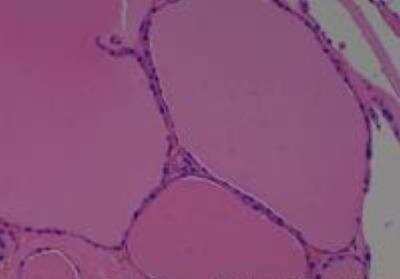

Hematoxylin & Eosin Stain: Human Common Tissue MicroArray (Normal Adjacent) [NBP2-30215] - 01. Stomach